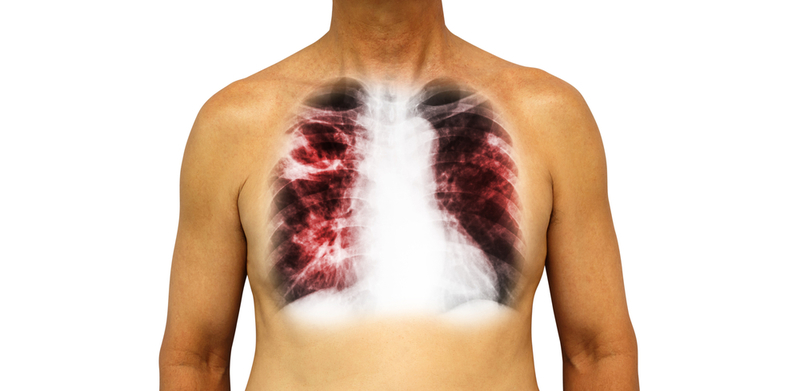

Novel tools could help treat patients with TB

New diagnostic tools such as Machine Learning and precision medicine could help identify tuberculosis patients with the highest risk of reactivation of the disease, say researchers.

Researchers from the University of Michigan in the US have shown that identifying multiple biomarkers can provide a more accurate diagnosis for patients with Latent Tuberculosis Infection (LTBI).LTBI is when a person is infected with Mycobacterium tuberculosis but does not have active tuberculosis.